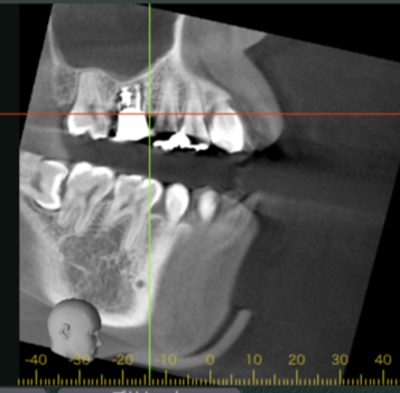

初診時CT画像

初診時デンタルX線写真とCT画像。

根管外に不透過像とそれを取り囲む透過像を認める。

コアを除去すると、分岐部へつながるパーフォレーションを認めた。

これが排膿の原因であったため、保存は困難と判断した。

移植12ヶ月後のCT画像①

移植12ヶ月後のCT画像②

移植12ヶ月後。CT画像では、歯根周囲に骨が形成されていることが確認できる。